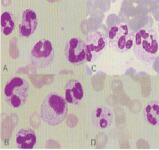

C、判斷垂體或腎上腺皮質(zhì)功能:腎上腺皮質(zhì)激素、垂體或腎上腺皮質(zhì)功能亢進時,嗜酸性粒細胞減低,因此,可通過垂體或腎上腺皮質(zhì)刺激試驗,觀察嗜酸性粒細胞數(shù)量變化,判斷垂體或腎上腺皮質(zhì)的功能。四、白細胞形態(tài)檢查:血涂片染色后,各種類型白細胞的形態(tài)學特點各不相同。在病理狀態(tài)下,除白細胞計數(shù)和分類發(fā)生變化外,其形態(tài)有時也會發(fā)生改變。計算各種白細胞比例及觀察白細胞形態(tài)的變化,對診斷疾病和觀察療效具有重要的意義。白細胞形態(tài)學檢查主要是顯微鏡檢查法。

(一)中性粒細胞毒性變化:在嚴重的化膿性感染、敗血癥、惡性腫瘤、急性中毒、大面積燒傷等病理情況下,中性粒細胞可發(fā)生一系列形態(tài)改變。這些形態(tài)變化對判斷預后有一定意義。

2、中毒顆粒:在嚴重感染及大面積燒傷等情況下,中性粒細胞的胞質(zhì)中出現(xiàn)比正常中性顆粒粗大、大小不等、分布不均的紫黑色或深紫褐色顆粒,稱中毒顆粒?赡芘c特殊顆粒生成過程受阻或顆粒變性造成2~3個嗜天青顆粒融合有關。含中毒顆粒的細胞在中性粒細胞中所占的比值稱為中毒指數(shù)。中毒指數(shù)愈大,感染、中毒情況愈嚴重。

(1)中毒顆粒較粗大且染色深,易與嗜堿性粒細胞的顆;煜。嗜堿性粒細胞胞核分葉較少,顆粒大而不均,染色更深,可分布在胞核上而使胞核分葉不清。

3、空泡形成:中性粒細胞的胞質(zhì)或胞核可出現(xiàn)1個或數(shù)個空泡。是細胞發(fā)生脂肪變性或顆粒缺失的結(jié)果,常見于嚴重感染、敗血癥等。EDTA抗凝儲存血中的細胞也可出現(xiàn)退行性空泡,此時,除非同時伴有其他中毒性形態(tài)改變,否則不宜將空泡變性歸因于中性粒細胞的毒性變。

4、杜勒小體:中性粒細胞因毒性變化而在胞質(zhì)中保留的局部嗜堿性區(qū)域(源自RNA),呈圓形、梨形或云霧狀,染天藍色或灰藍色,直徑0.1~2μm,最大可達5μm,單個或多個,常位于細胞邊緣,超微結(jié)構(gòu)顯示,為粗面內(nèi)質(zhì)網(wǎng)組成,與正常染色區(qū)域界限模糊,是胞質(zhì)局部不成熟即核質(zhì)發(fā)育不平衡的表現(xiàn)。常見于嚴重感染,如肺炎、麻疹、敗血癥和燒傷等。

5、退行性變:退行性變是細胞發(fā)生胞體腫大、結(jié)構(gòu)模糊、邊緣不清晰、核固縮、核腫脹和核溶解(染色質(zhì)模糊、疏松)等現(xiàn)象,常見于衰老和病變的細胞。

(二)棒狀小體:白細胞胞質(zhì)中出現(xiàn)的紅色細桿狀物質(zhì),1個或數(shù)個,長約1~6μm,稱為棒狀小體(圖2-33),是初級嗜天青顆粒結(jié)晶化的形態(tài)。棒狀小體對鑒別急性白血病的類型有重要價值,主要見于急性粒細胞白血。ǘ嘁姡┖图毙詥魏思毎籽。ㄉ僖姡,而急性淋巴細胞白血病則無。

(三)中性粒細胞的核象變化:核象標志著中性粒細胞從新生細胞以至衰老細胞的發(fā)育階段。正常情況下,外周血中性粒細胞以分葉核為主,胞核常分為2~5葉,桿狀核較少,分葉核與桿狀核中性粒細胞的比值為13∶1。病理情況下,中性粒細胞的核象可發(fā)生核左移或核右移。

1、核 左 移:外周血中性桿狀核粒細胞增多或(和)出現(xiàn)晚幼粒、中幼粒甚至早幼粒細胞的現(xiàn)象稱為核左移。核左移是機體的一種反應性改變,常見于化膿性感染、急性溶血以及應用細胞因子,如粒細胞集落刺激因子或粒細胞巨噬細胞集落刺激因子等,并伴有中毒顆粒、空泡、退行性變等毒性變化。核左移常伴有白細胞總數(shù)增高,但白細胞總數(shù)也可正常甚至減低。核左移分為輕、中、重度三級,與感染嚴重度和機體抵抗力密切相關。